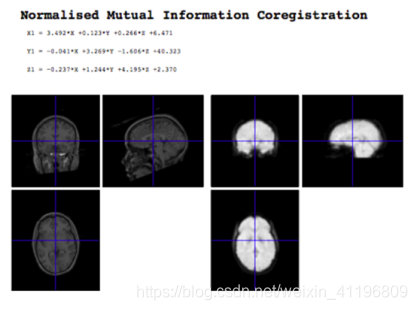

四、Co-registration

接下来的事情就是结构图像与功能图像配准(Co-registration)了。我们希望能把功能图像上的点定位在有着较高分辨率的结构图像上。

虽然我们分析的是较低分辨率的功能图像,但当我们将其定位在结构图象上时,我们可以发现一些更细节的问题。配准也为我们之后要讲到的标准脑(Standard coordinate system)提供了很大的帮助。

一般来说我们会在实验的每轮扫描的开始扫一张结构图像。虽然说结构图像和功能图像是在同一论扫描里扫得的。但往往它们往往是没法重合覆盖在一起的。一是因为他们测量不是一个东西(编者注:一个是组织一个是血流信号),二是因为测量过程中会有头动。

结构图像和功能图像有这么几个区别:

信号的数量级不一样,没法直接对比

形状不一样。至少要用仿射变换才能配在一起。在这里我们一般使用Mutual Information 来作为代价函数

注:软件SPM算出的配准变换方式。